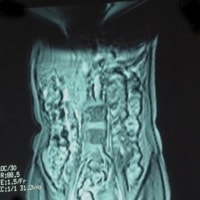

患者様を案内又は搬送する際は、患者様の金属の有無について十分注意をお願いします。金属が体内に入っている方や、 身につけている方は写真上に影響が出ると同時に体内金属が動いたり、発熱したりする場合があり危険な場合があります。 金属があった場合の症例を提示します。

下着の金具による影響